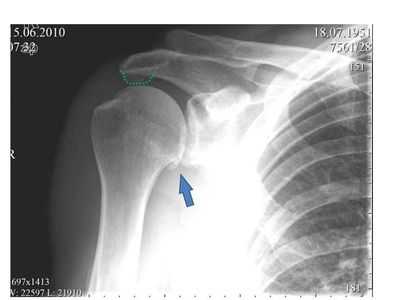

2. Рентгенография при внутреннем импиджменте плечевого сустава:

• Молодой пациент с задними кистами и/или склерозом головки плечевой кости

• Заднее углубление головки плечевой кости: псевдоповреждение Хилла-Сакса:

о Малое, на том же месте, что и кисты

о ± повреждение Беннетта (оссификация задней капсулы плечевого сустава)